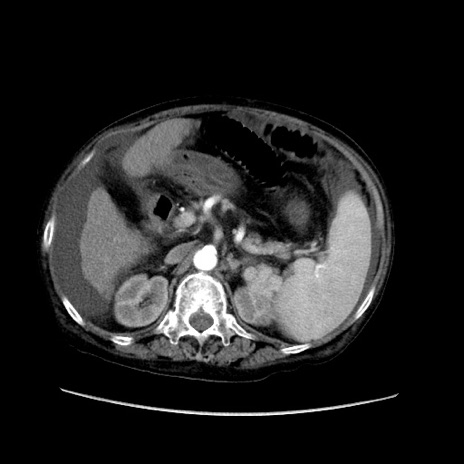

症例31(横断像)

【症例】80歳代 女性

【主訴】腹部膨満感

【現病歴】他院にて肝硬変にてフォロー中。1週間前から便秘、腹部膨満感、臍部腫瘤あり受診となる。

【既往歴】肝硬変

【身体所見】腹部膨隆あり、皮膚変化なし、疼痛なし。

【データ】WBC 4600、CRP 0.25